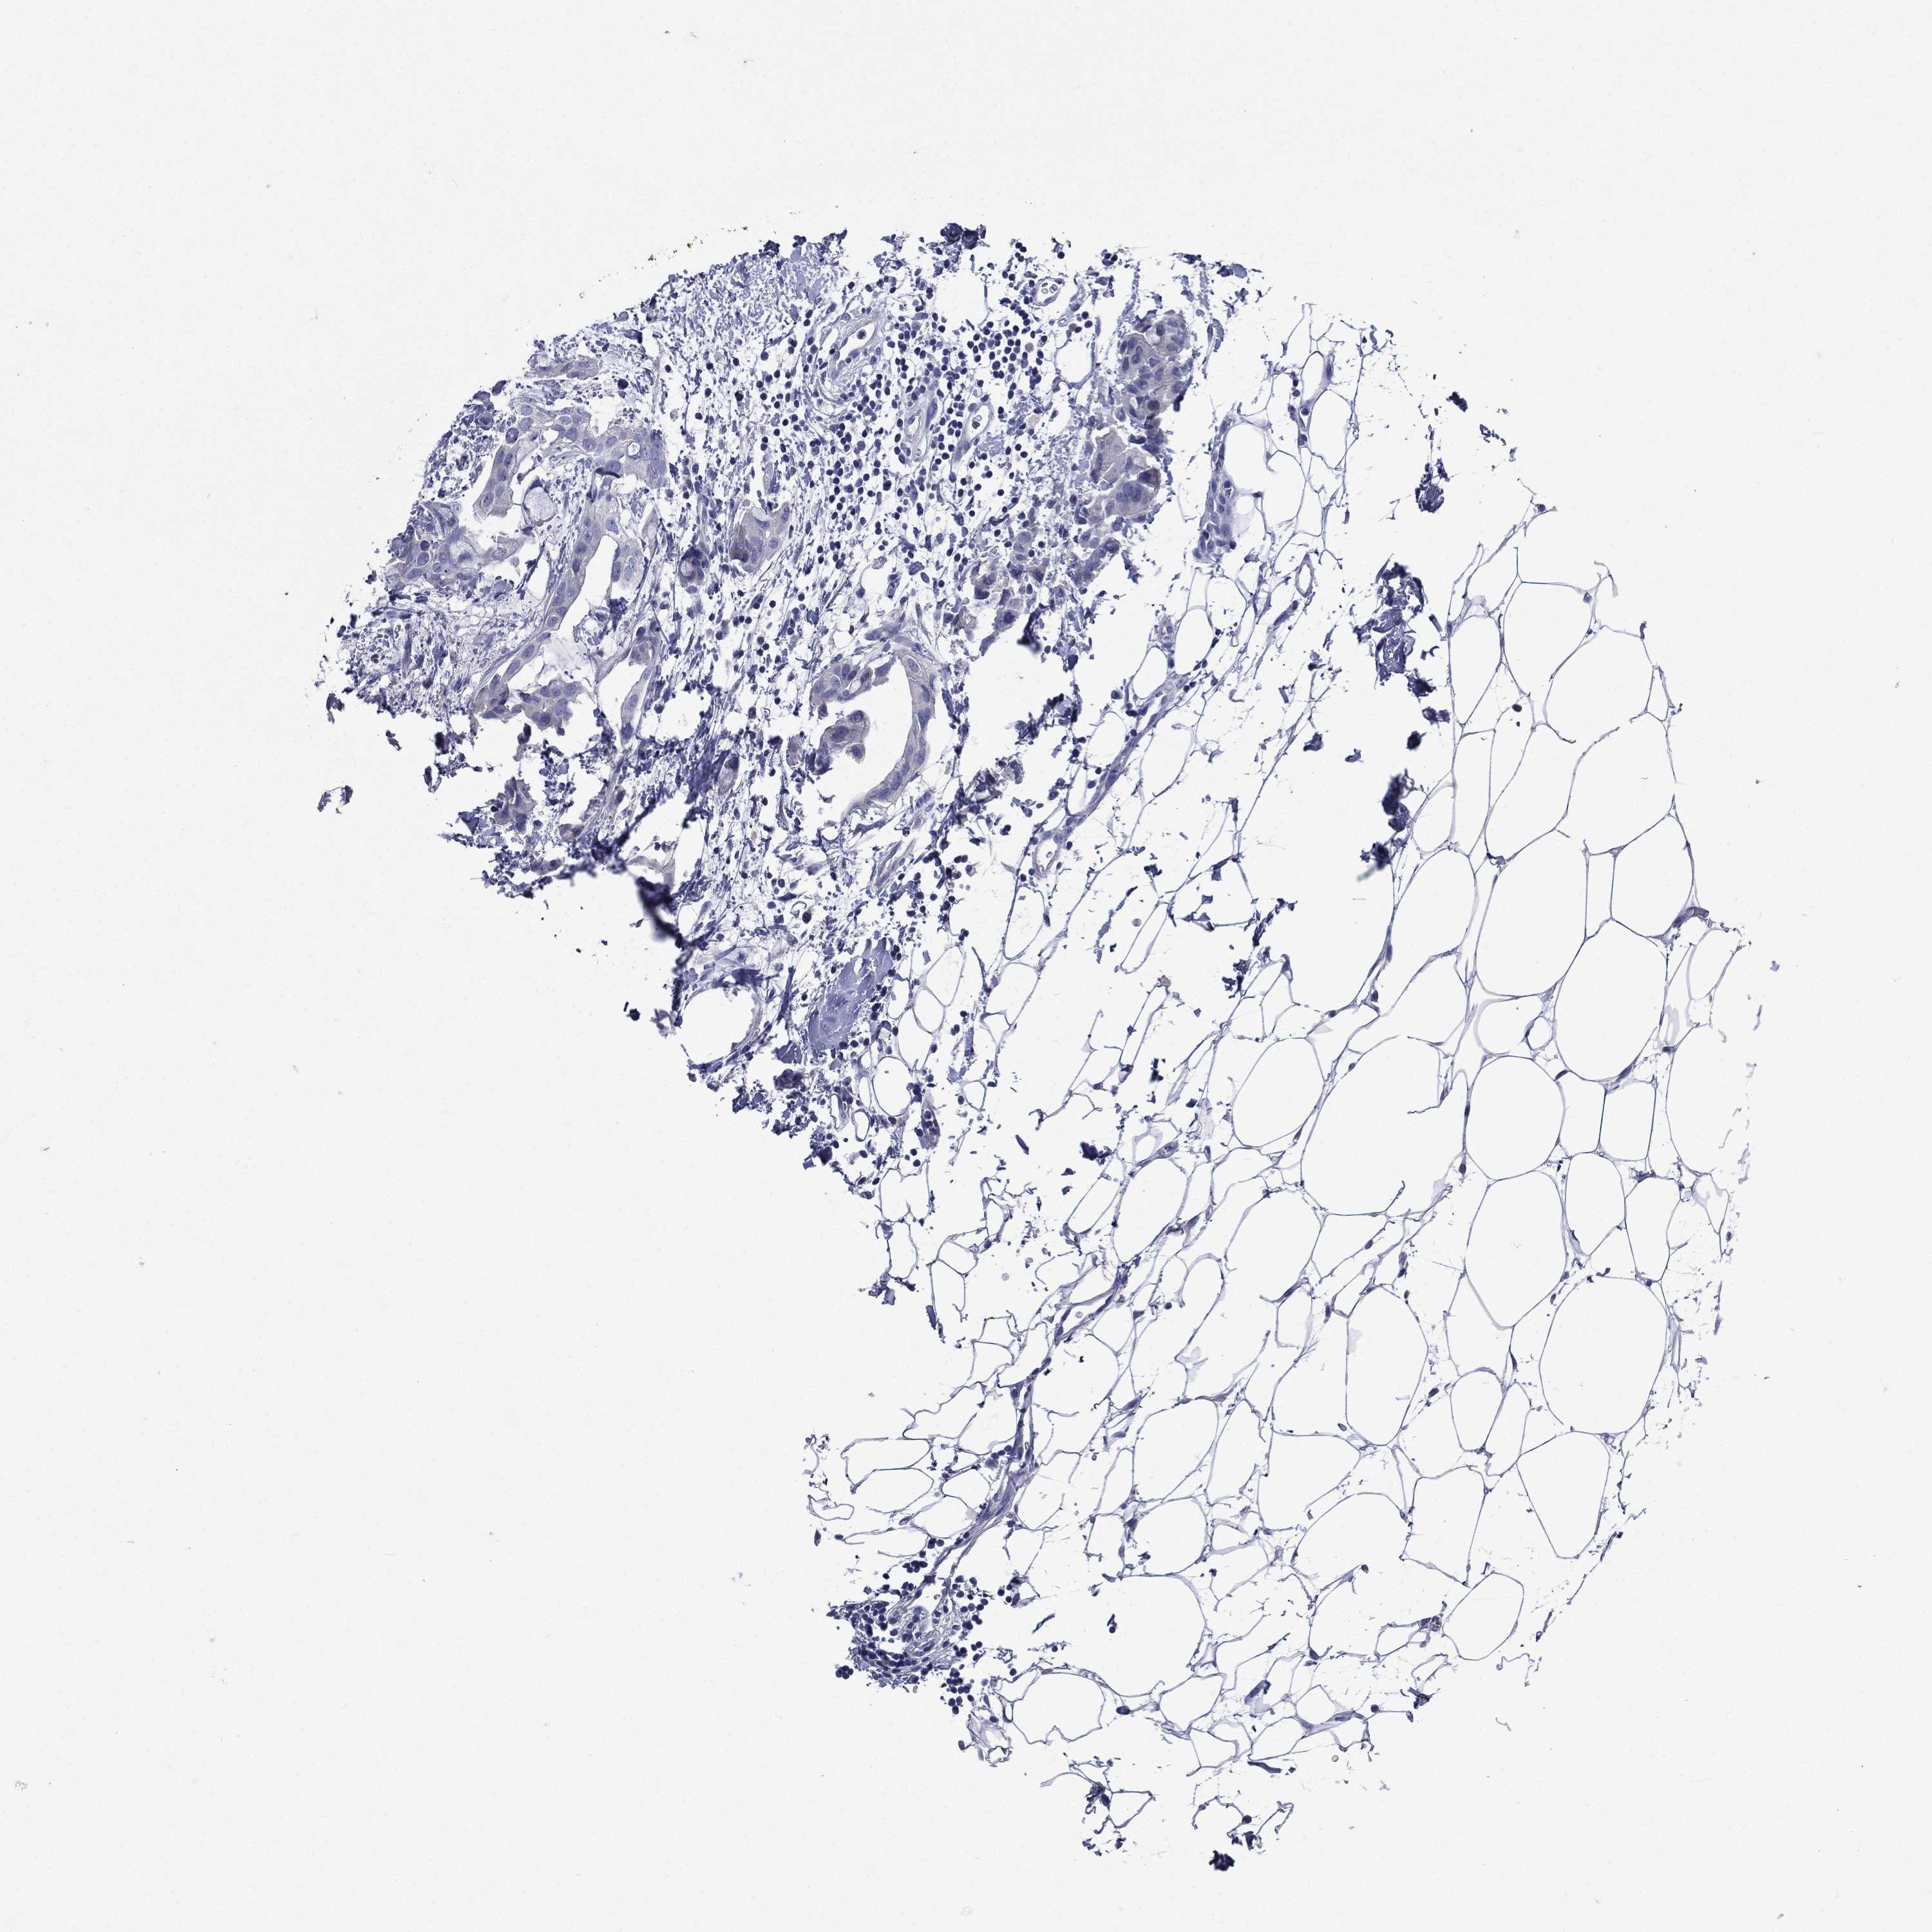

CANCER BREAST CANCER Show tissue menu

BRCA TCGA BRCA VALIDATION PROTEIN EXPRESSION